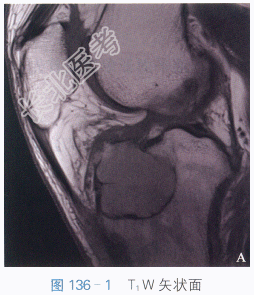

T₁W矢状面(见图136-1),胫骨平台多房性骨破坏,境界清楚,呈低信号影,病灶周围可见薄层线状更低信号影。T₂W矢状面脂肪抑制(见图136-2),病灶内见多房性伴“液液”平面。横断面STIR(见图136-3),病灶内见多房性伴“液-液”平面。

读片分析:该组案例MRI检查表现为胫骨平台局部膨胀,病灶呈多房改变,分隔较厚,病灶边界清。矢状面T₂W脂肪抑制可以看到病灶内部“液-液”平面,为动脉瘤样骨囊肿特征性表现。